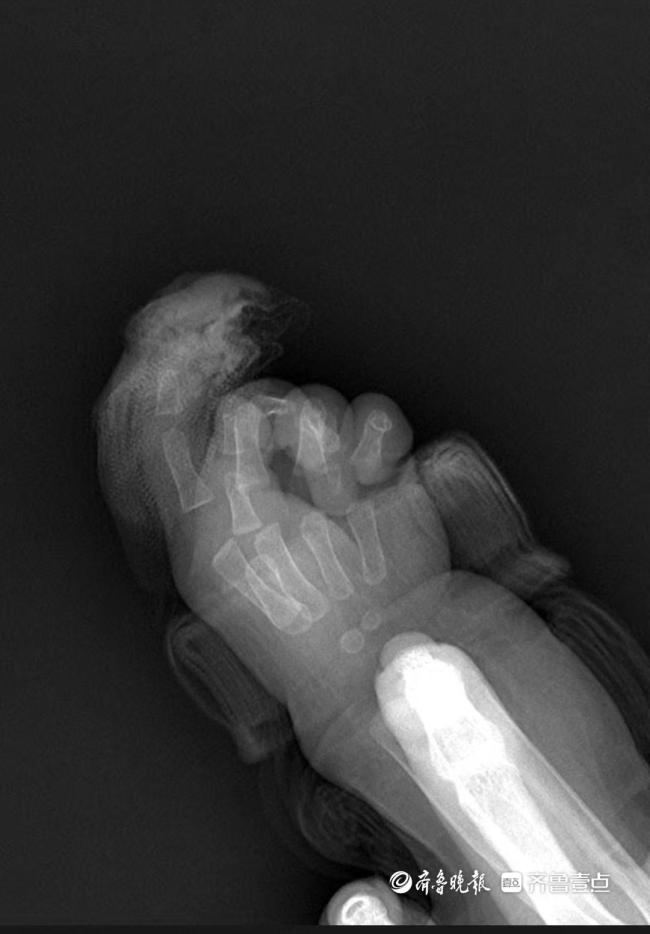

“绣花式”手术为7月龄女婴断指再接 显微镜下极限挑战

4月15日下午,在济南市第三人民医院手及上肢外科病房内,7个月大的芙芙正好奇地打量着周围,她的右手缠着厚厚的无菌纱布。11天前,这个刚萌出两颗乳牙的女婴经历了一场断指再植的极限救援——她的右手食指第一关节被剪刀完全剪断。

急诊就诊时间是9时22分,同步启动术前准备。手及上肢外科主治医生王思月回忆,急诊团队第一时间为芙芙止血、抽血、做心电图和拍片,“孩子伤口还在渗血,更换了3次纱布,同时输液,避免脱水。”